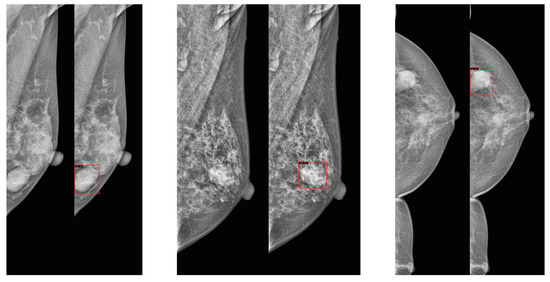

We used four public mammography datasets. The summary of the datasets is provided in Table 1. Masses and calcifications were chosen as the target lesions due to their high clinical relevance in breast cancer screening, as they are the most common abnormalities detected in mammography and are consistently annotated across all four datasets. In addition, example images are provided in Figure 1.

Figure 1. Examples of craniocaudal (CC) and mediolateral oblique (MLO) view pairs from mammography datasets. (top left): VinDr-Mammo, (top right): INbreast, (bottom left): CBIS-DDSM, (bottom right): EMBED. In each pair, the MLO view is shown on the left and the CC view on the right.